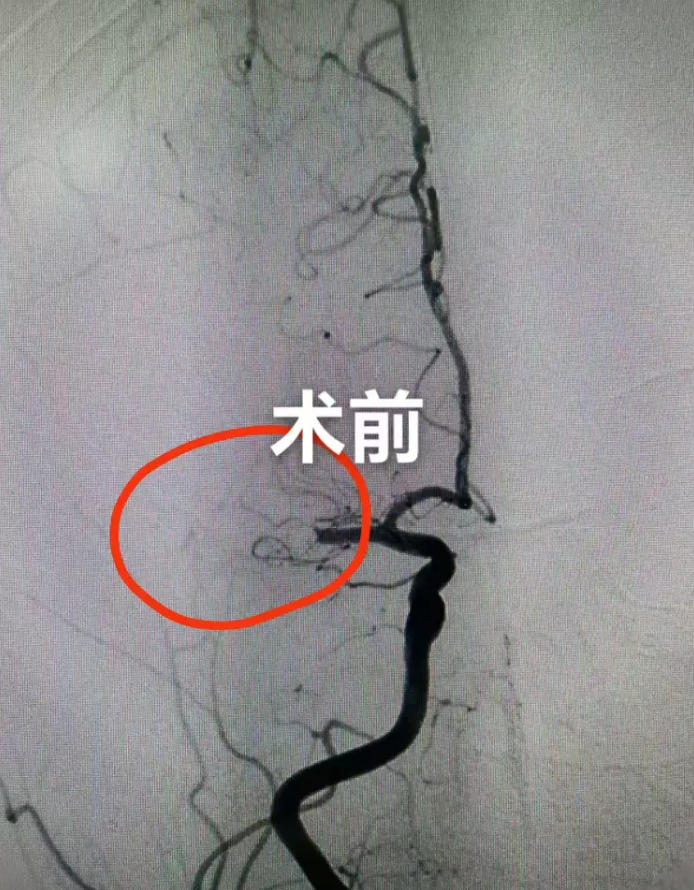

患者抵达医院后,神经内科医生立即予以静脉溶栓治疗,溶栓后患者左侧肢体力量有所改善。经头颈部CTA检查,确诊为右侧大脑中动脉M1段闭塞。神经介入团队当机立断,立即桥接进行动脉介入取栓治疗。手术顺利,闭塞血管成功再通。术后第1天,患者神志恢复,左侧肢体肌力恢复至4级,可抬举与持物。多次复查头颅CT未见出血转化,为后续抗凝治疗打下良好基础。